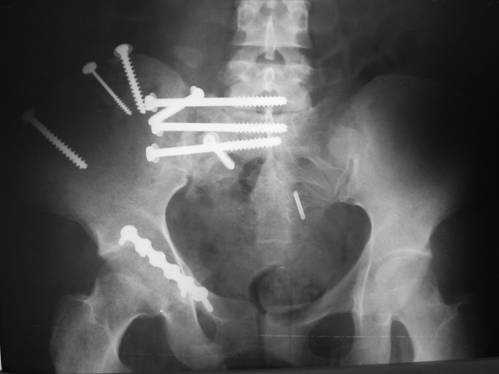

23.09.2003. Одновременный остеосинтез переднего и заднего тазовых полуколец

Результат через 10 дней

и 8месяцев после операции